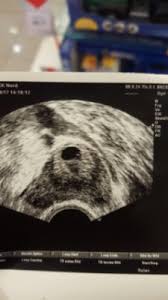

Was ist eine bauchhöhlenschwangerschaft. Die Bauchhöhlenschwangerschaft wird in der Fachsprache auch als Extrauteringravidität EUG bezeichnet. Eine sehr seltene Bauchhöhlenschwangerschaft ist wie die Eileiterschwangerschaft eine Form von Extrauteringravidität. Bei den betroffenen Schwangeren hat sich die befruchtete Eizelle nicht in der Gebärmutter sondern in der freien Bauchhöhle eingenistet.

Eine Bauchhöhlenschwangerschaft kommt nur bei etwa 1 aller Schwangeren vor. Die Bauchhöhlenschwangerschaft ist wie die Eileiterschwangerschaft eine Form von Extrauteringravidität Schwangerschaft außerhalb der Gebärmutter. Die befruchtete Eizelle fällt dabei durch die obere Öffnung des Eileiters in die Bauchhöhle und nistet sich hier ein - meist an der Darmwand oder der Rückwand der Gebärmutter.

Die Bauchhöhlenschwangerschaft ist eine seltene Form der Extrauteringravidität bei der sich die befruchtete Eizelle außerhalb der Gebärmutter in der Bauchhöhle einnistet meist als Folge einer Adnexitis mit Verklebung der Tuba uterina. Die befruchtete Eizelle nistet sich nicht wie vorgesehen in der Gebärmutter ein sondern heftet sich in der Bauchhöhle fest. Bei allen anderen Formen stirbt er aufgrund von Nährstoffunterversorgung.